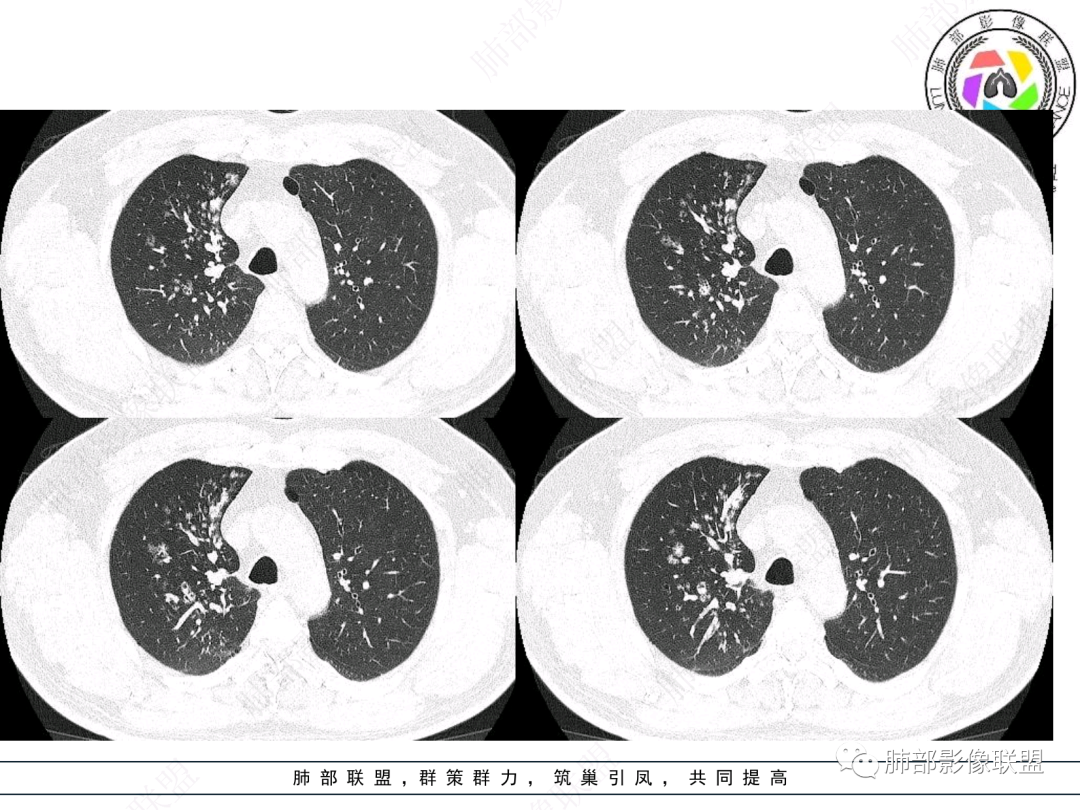

右肺上叶支气管截断,内见软组织密度结节,支气管管壁破坏,病变侵及管外,增强强化明显。右肺上叶沿气管血管束多发斑片影,考虑恶性性病变并阻塞性炎症,鳞癌,神经内分泌肿瘤。

右肺门病灶,支气管腔内堵塞,见有多处低密度影,支气管镜下凹凸不平,直观下不像鳞癌,恶性肯定的,考虑腺样囊性癌可能。

右肺主支气管-上叶支气管腔内结节伴钙化,轻度强化,考虑类癌,鉴别错构瘤与结核。

老年男性,咳嗽咳痰,右肺门增大,右主支气管开口见高密度影,密度不均匀,轻度强化,右肺上叶见多发腺泡结节,支气管管壁增厚,近端粘液栓,支气管镜检查见新生物,考虑鳞癌,鉴别结核。

右主支气管及肺门不规则软组织结节,点状钙化,不均匀强化,气管壁破坏,上叶支气管阻塞,分支粘液栓,血管束增粗,沿支气管分布多发结节,考虑鳞癌合并阻塞性炎症,鉴别结核。

右气管腔内结节,右肺门肿物,有钙化,右侧肺内多发气腔结节,散在,左肺部分支气管壁增厚,首先分析气管内结节,多考虑1鳞癌,形态规则,边缘光滑,宽基底,不太支持,远端阻塞性炎症不典型,2类癌,冰山一角和冰山分离了,不太支持3结核,多为支气管壁广泛增厚钙化,形成结节少,但是肺门肿块有钙化,可作为结核支持点,4黏痰,不像。其他不太懂了,肺内多发磨玻璃结节,并可见支气管手指状扩张,综合分析影像,考虑感染性病变,结核?有没有这样子的气管曲霉呢?向老师们学习。

老年男性,右肺门主支气管腔内软组织肿块影,密度不均,有钙化,右上叶支气管腔部分阻塞,强化较明显,右肺上叶远端散在斑片状高密度影,相应支气管壁厚,树丫状腺泡结节,常规首先考虑结核,鉴别类癌。

右主支气管占位,累及全层,中度强化,远端管壁增厚,似乎花花草草,恶或者低度恶性。疾病谱:鳞(必须首先考虑 概率),腺样囊腺癌(位置 年龄符合 似乎强化也符合),类癌(强化不太支持),良性,结核(妖)。综合考虑腺样囊腺癌。

男性,52岁,右侧主支气管腔内外占位伴点状钙化,病灶大部分位于腔外,右肺上叶散在结节影,气管腔内病灶,动脉期中度强化,静脉期强化减低,首先考虑气管腔内类癌可能,鉴别鳞癌,肺内病变倾向感染性病变;再有气管结核伴肺内播散。

男,52。间断咳嗽、咳痰2周,加重3天。胸部CT:右主、右上叶支气管多发软组织影,跳跃不连续,内可见小环状高密度,点状钙化,管壁破坏,上叶支气管堵塞,远端分支粘液栓,可见小支气管管壁增厚、管腔狭窄,沿支气管分布多发结节,无大片炎症不张。考虑:TB?NTM?鉴别Ca并阻塞性炎症。

肺门肿块,支气管铸型,远侧小花小草,考虑鳞癌,右主支气管结节,鳞癌?二元论:腺样囊性癌?

中年男性,咳嗽咳痰,右肺上叶近肺门肿块,上叶支气管近端阻塞,内有粘液栓,右肺上叶多发结节影有小空泡,沿支气管血管束分布,血象不高,CRP及PCT不高,XPERT阴性,结核可能性不大,考虑恶性肿瘤可能,类癌?腺样囊性癌?鳞癌?远端肺内的考虑阻塞性炎症还是转移?

患者中老年男性,咳嗽咳痰2周,无发热、咯血,伴胸闷、乏力及盗汗等,右上叶沿支气管血管束分布结节样变,管壁增厚;右肺门肿块,形态不规则、密度欠均匀,似有钙化,轻强化,主气道下端及右主支气管开口处见新生物,强化不支持类癌,镜下病变形态不大支持腺样囊性癌,考虑鳞癌可能性大,右肺上叶病变结核可能。

右肺上叶支气管开口见阻塞物影及强化,息肉样向腔内外浸润性生长,并有颗粒钙化,右肺上叶段支气管主干增粗及密度增高,见指套征,支气管血管旁见多发小斑点,小斑片影阻塞性炎性病灶〈小花小草表现〉,支气管镜示新生物血供丰富(结核完全排除),方向恶性,符合鳞癌特点,与小细胞Ca鉴定,临床专科支气管镜取材活检明确诊断。

腔内肿物,强化不均匀,强化程度为轻中度强化(CT值增加25HU),且强化特点为快进快出,右肺上叶支气管责任区域的阻塞性炎症加痰栓(气管镜也证实右上叶支气管内痰多)。这些均明确指向鳞癌。

屈运良:

毛勤香:

这个病例比较好,我们的观察点在哪?这是右上叶支气管病变,需要了解:腔内、壁、腔外、远端,腔内有软组织密度影,近端膨隆。